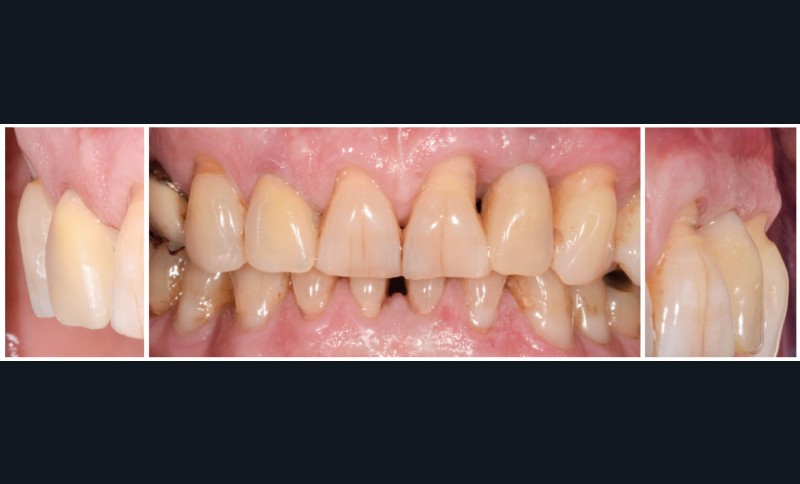

Traitement

Au vu des conditions initiales, il nous apparaît impossible de restaurer une esthétique satisfaisante, notamment au niveau de l’alignement des collets, sans une chirurgie muco-gingivale associée à une réhabilitation des dents antérieures par facettes. En effet, la perte de la 22, associée à une forme triangulaire des dents, a provoqué un non-alignement des collets ainsi que la présence de trous noirs entre les dents 21-22 et 22-23. Cependant, les contraintes exprimées par le patient contre-indiquaient ce traitement.